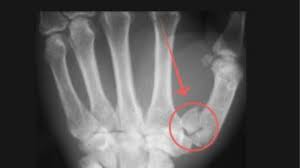

Bennet's Fracture

Oblique, vertical 1st metacarpal with dorsal dislocation.